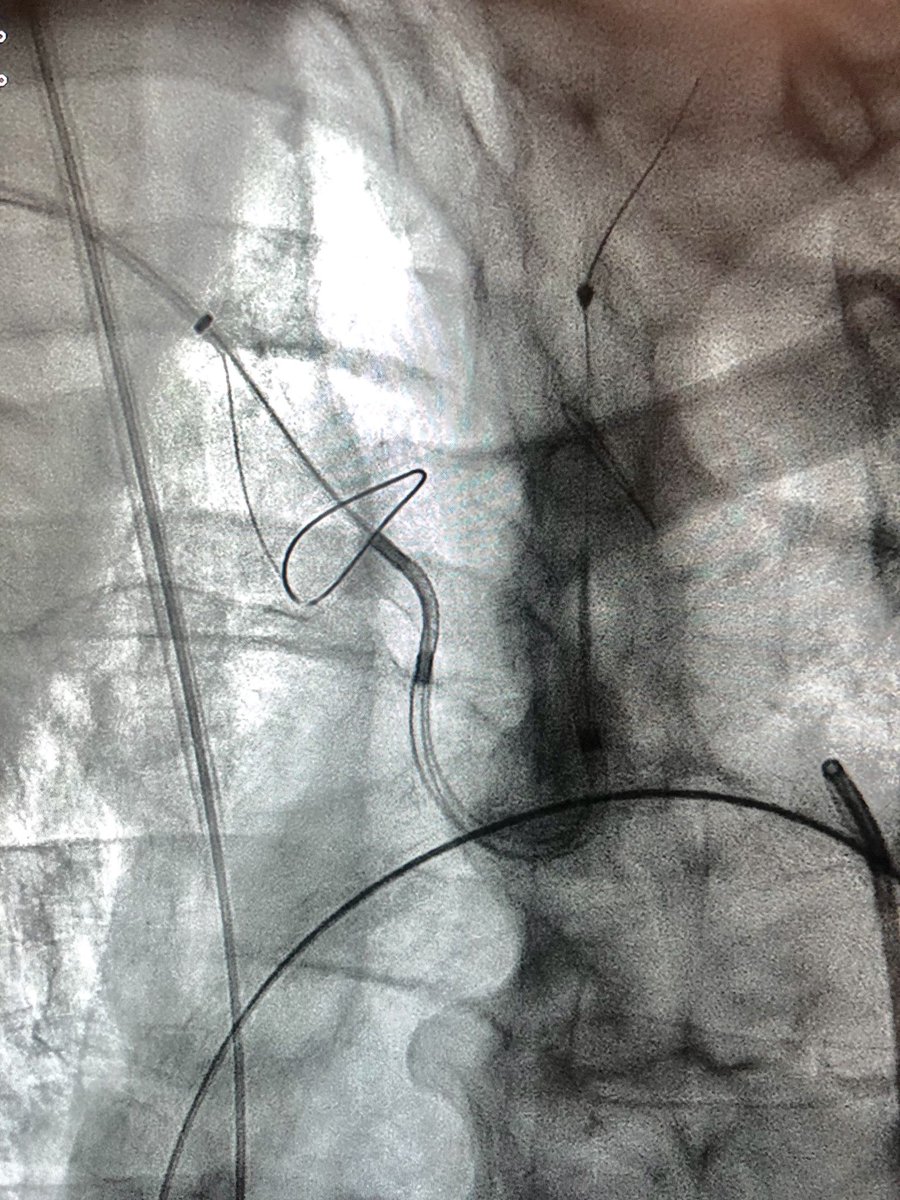

Successful live case transmission from @KarolinskaUnsju to PAFCIC conference in Tunisia today. #tavr using #Acurate, LV wire pacing, #sentinel neuroprotection. Honored to be followed by Alain Cribier in the program. Operators Nawzad Saleh and myself.